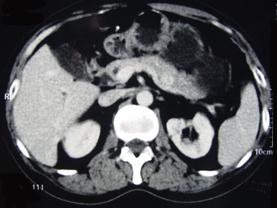

问题 男性,57岁,1年前无明显诱因反复出现嗜睡及发作性神志不清,进食糖水或甜品后症状即缓解,腹部CT检查如下图,最佳的诊断是() {图} {图1} {图3}

选项 A.胰腺癌 B.胰岛细胞瘤 C.胰腺转移瘤 D.胃泌素瘤 E.舒血管活性肽瘤

答案 B